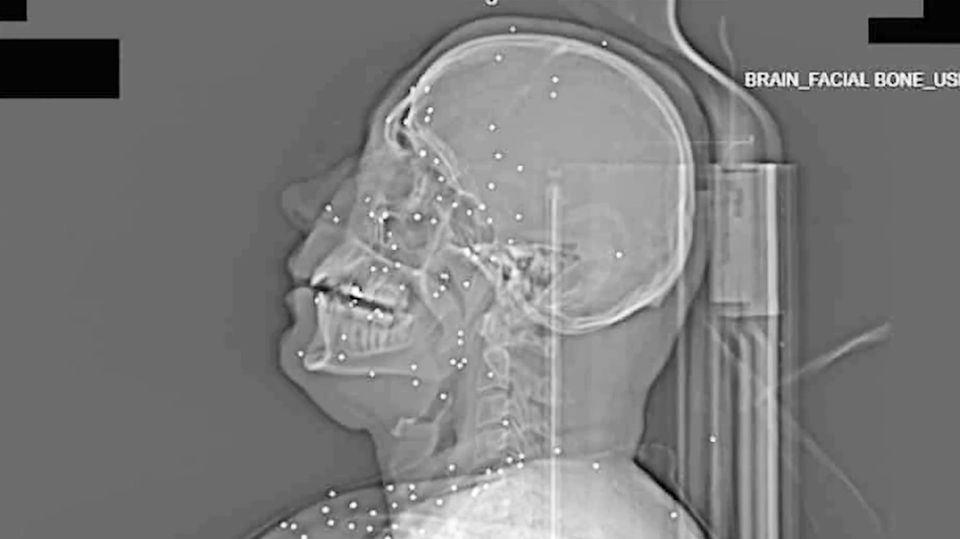

Ein Röntgenbild einer Person, die angeschossen wurde.

75 Röntgen- und CT-Bilder aus einer iranischen Klinik zeigen, wie brutal das Regime gegen Protestierende vorgeht. Sie wurden mutmaßlich in nur einer Nacht im Januar aufgenommen.